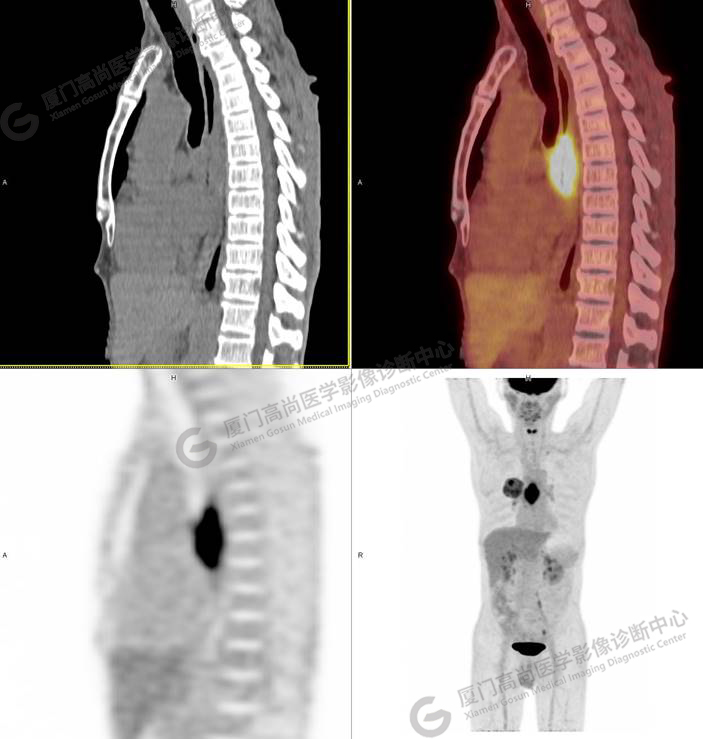

矢狀位清晰顯示,食道病灶累及長度約6cm

我中心醫(yī)師考慮張先生還有食道癌的可能性,故詢問張先生近期飲食情況,張先生表示近3個(gè)月進(jìn)食哽噎感,目前流質(zhì)飲食,加之影像學(xué)和臨床表現(xiàn)都符合食管癌!這位先生是同時(shí)罹患了兩種原發(fā)腫瘤嗎?